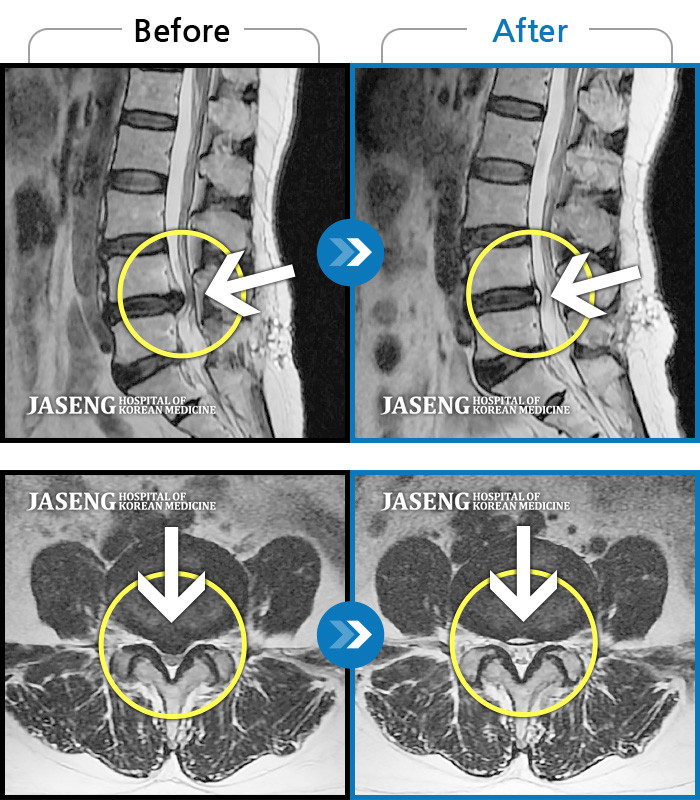

MRI사진에서 좋아지고 있다는 말씀에 넘 기뻤습니다^_^

처음 자생한방병원 강남본원을 방문해서 기존 양방병원에서 수술하고 치료받았던 MRI랑 CT자료를 가지고 사전 상담해주셨던 분에게서 받았던 인상(질문하시면서 좀 고압적이고 딱딱하게 대하셨던 느낌)때문에

제가 가지고 간 MRI 영상자료를 보시면서 수술하지 않고도 충분히 고칠수 있다는 희망적인 말과 증상에 대해 자세히 설명해주시고 앞으로 어떻게 치료할 것인지에 대하여 알기쉽게 설명해주셔서 감사했습니다.